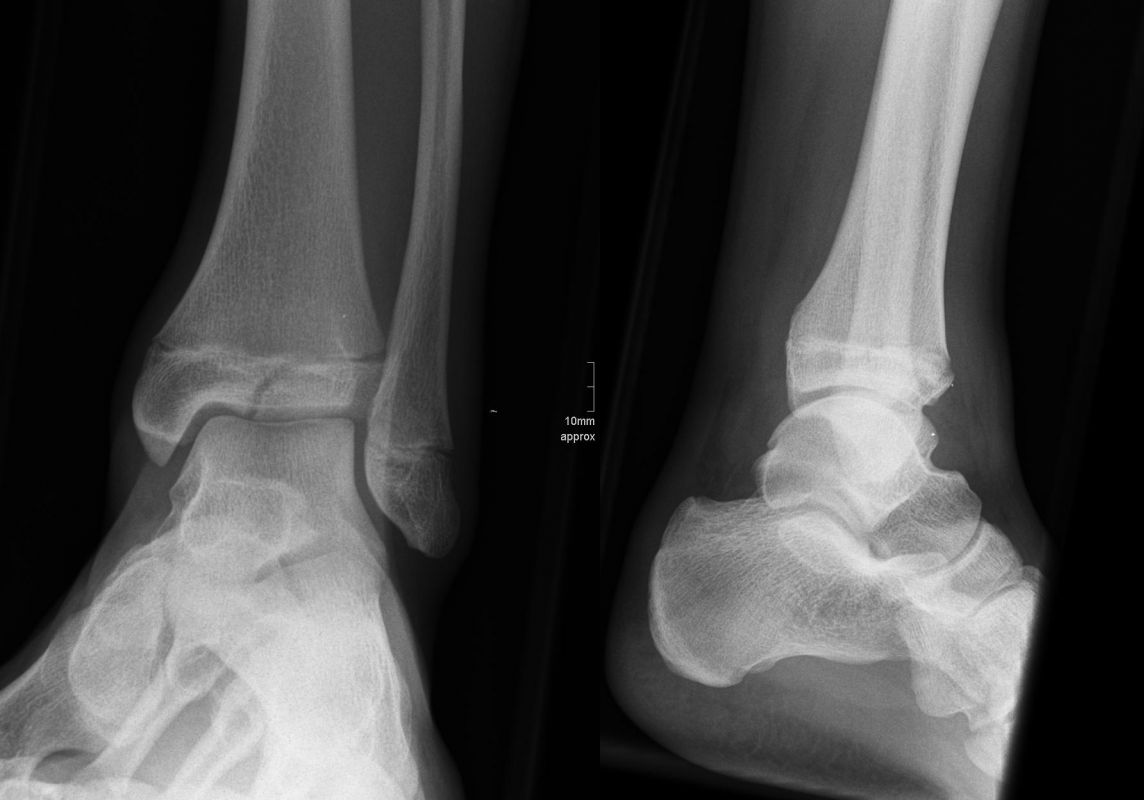

Fugengelenkfrakturen treten typischerweise vor dem 10. Lebensjahr auf, in einer Phase, in welcher die Wachstumsfugen noch weit offen sind. Dieser Frakturtyp betrifft fast ausschließlich den medialen Malleolus. Laterale Frakturen sind extrem selten, teilweise kommt es zu lateralen Bandverletzungen oder Fugenschaftfrakturen der distalen Fibula. Die Frakturlinie verläuft in einer Verlängerungslinie von der medialen Taluskante nach proximal. Häufig stellen sich Verletzungen des Innenknöchels im Röntgenbild schlechter dar, insbesondere wenn die Aufnahmen verdreht sind oder die Ebene der Fraktur bei geringer Dislokation verkippt zur Röntgenebene liegt. Besteht klinisch der geringste Hinweis auf eine Verletzung des Innenknöchels, muss aufgrund der Tragweite der Verletzung durch entsprechende Aufnahmen gegebenenfalls auch Schnittbildverfahren die Verletzung sicher diagnostiziert oder ausgeschlossen werden (Abb. 15).

Fugengelenkfrakturen können die Wachstumsfuge durchkreuzen (Abbildung 16a), ohne oder nur mit minimaler Beteiligung der Fuge sehr weit medial liegen (Abbildung 16b) oder durch die Fuge auslaufen (Abbildung 16c). Relevant für die Wachstumsprognose ist weniger die Form der Fraktur, sondern das Alter des Patienten zum Zeitpunkt des Traumas sowie das Ausmaß der Schädigung der Wachstumsfuge, wobei eine Korrelation mit dem Ausmaß der Dislokation besteht.